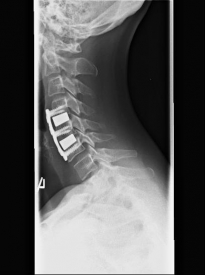

Spinalkanalstenose IISpinalkanalstenose III

MRI with lateral reconstruction of the cervical spine and a lateral postoperative radiographic check. On the left, an hourglass-shaped constriction of the spinal cord can be seen. The right image shows the condition after surgical decompression and stabilization.